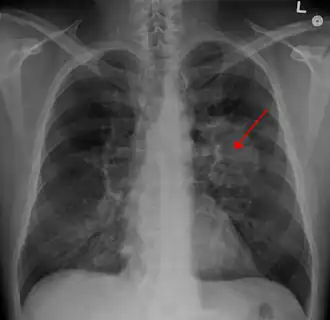

| Рентгенограмма грудной клетки, демонстрирующая опухоль в лёгких | |

Рентгенологическое исследование является одним из основных методов диагностики опухолей лёгкого и позволяет своевременно обнаружить его у 80 % больных. В качестве скринингового метода используется флюорография, которая обычно проводится во время профилактических медосмотров. При выявлении изменений (солитарный лёгочный узел, ателектаз и т. д.) на флюорограмме или при наличии клинических показаний применяют рентгенографию в двух проекциях и компьютерную томографию. Кроме того, компьютерная томография является наиболее информативным методом диагностики метастазов в других органах.